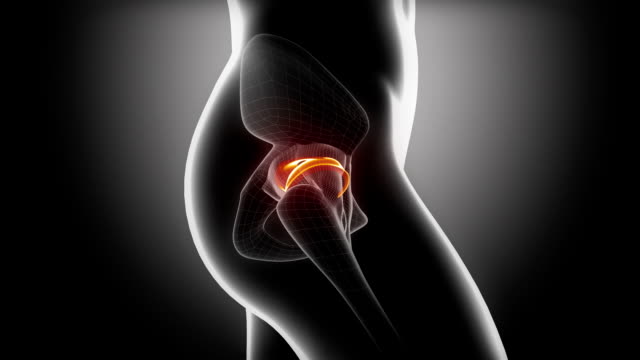

고관절 수술 후 회복에 필요한 시간을 알려드려요. 고관절 수술은 고관절의 변화로 인한 통증 및 기능 장애를 개선하기 위해 수술적인 처리를 하고, 수술 후 환자들은 회복 기간을 거치게 됩니다.

이 글에서는 고관절 수술 후 회복 기간과 주의사항에 대해 알려드리도록 하겠습니다.